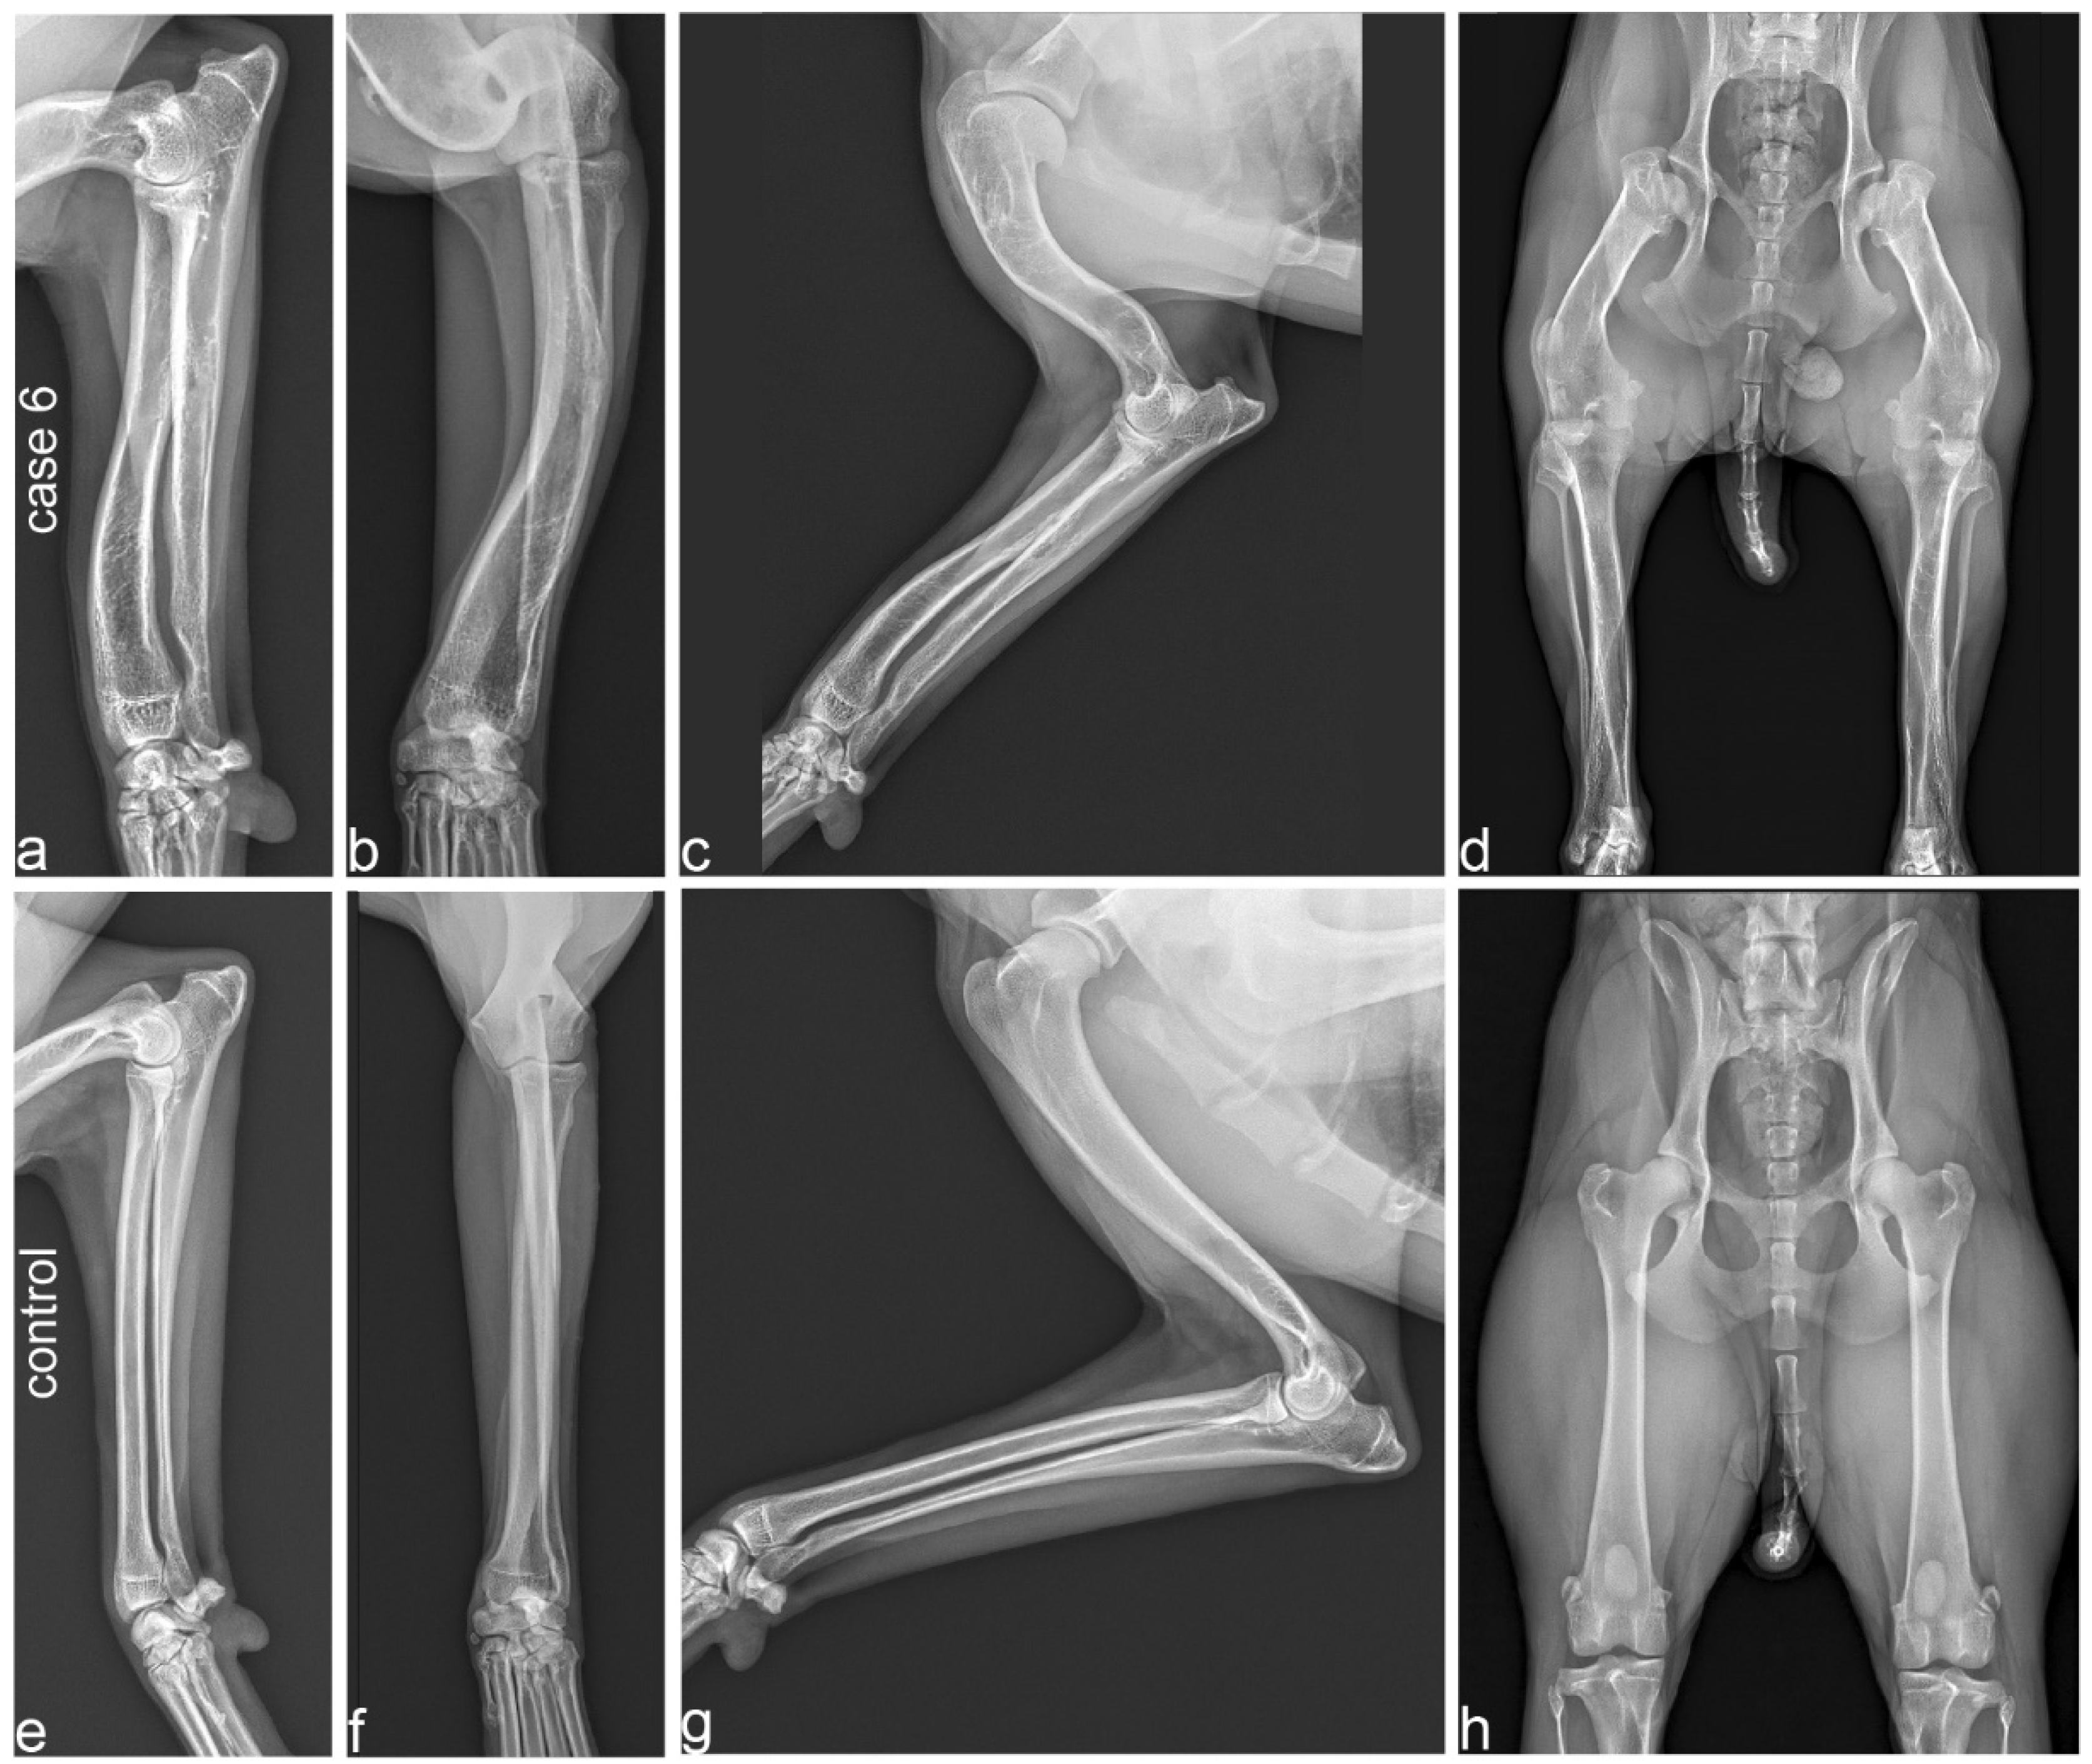

Radiographs from three affected (cases 4, 6, 8) and two unaffected dogs were available. The radiological findings in the affected dogs indicated variable severity of the skeletal changes.

In case 6, angular limb deformity with procurvatum of both humeri and procurvatum and varus deformity of both radii was noted (Figure 3a,b). Varus of both tibiae was also visible with marked thickening and shortening of long bones. In particular, the humeri and femora showed shortening, resulting in a shorter brachium in relation to the antebrachium and a shorter thigh in comparison to the lower leg (Figure 3c,d). The humerus and femur showed marked thickening of the epiphysis with a flattened articular surface (Figure 3c,d). In case 4, the thickening and shortening was less obvious, but the humerus, radius and ulna showed a procurvatum.

Figure 3.

Radiographs of a 2-year-old affected Vizsla (case 6; a–d) and its 3-year-old unaffected half-sister (e–h). (a,b) Orthogonal radiographs of the radius and ulna in case 6 show procurvatum and varus deformity, and thick and short bones. (c) Humerus and antebrachium of the affected Vizsla. Note the marked deformity and shortening of the humerus, flattened articular surface and deformity of the humerus. (d) Extended hip radiograph of the affected dog. Note the marked shortening and deformity of the femur, including its epiphysis, resulting in subluxation of the hip joint and secondary deformity of the acetabula. (e,f) Orthogonal radiographs of the radius and ulna. All long bones of the unaffected control dog demonstrate a normal limb axis and normal relation between the length and thickness of the bones. (g) Humerus and antebrachium of the unaffected control. (h) Extended hip radiograph of the unaffected dog. Please note that the scale of the radiographs is not standardized.